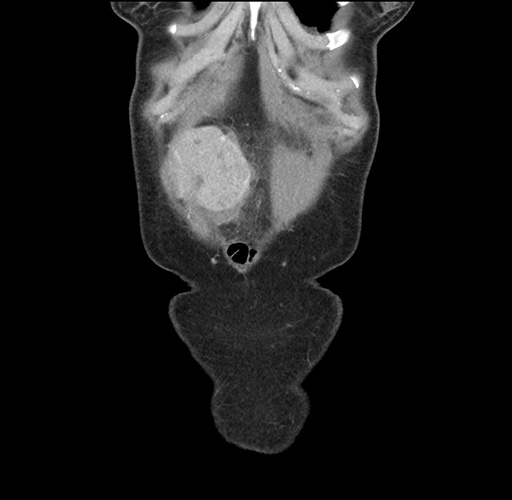

Imaging Analysis

Look through the patient's CT scan to identify any areas of concern for the necessary procedure.

Based on your CT findings, which issue(s) would give reason for "planned slowing down moment(s)" in this case?